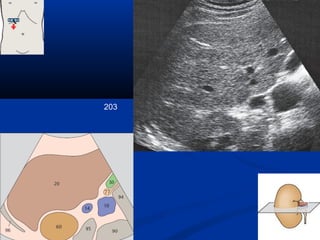

203